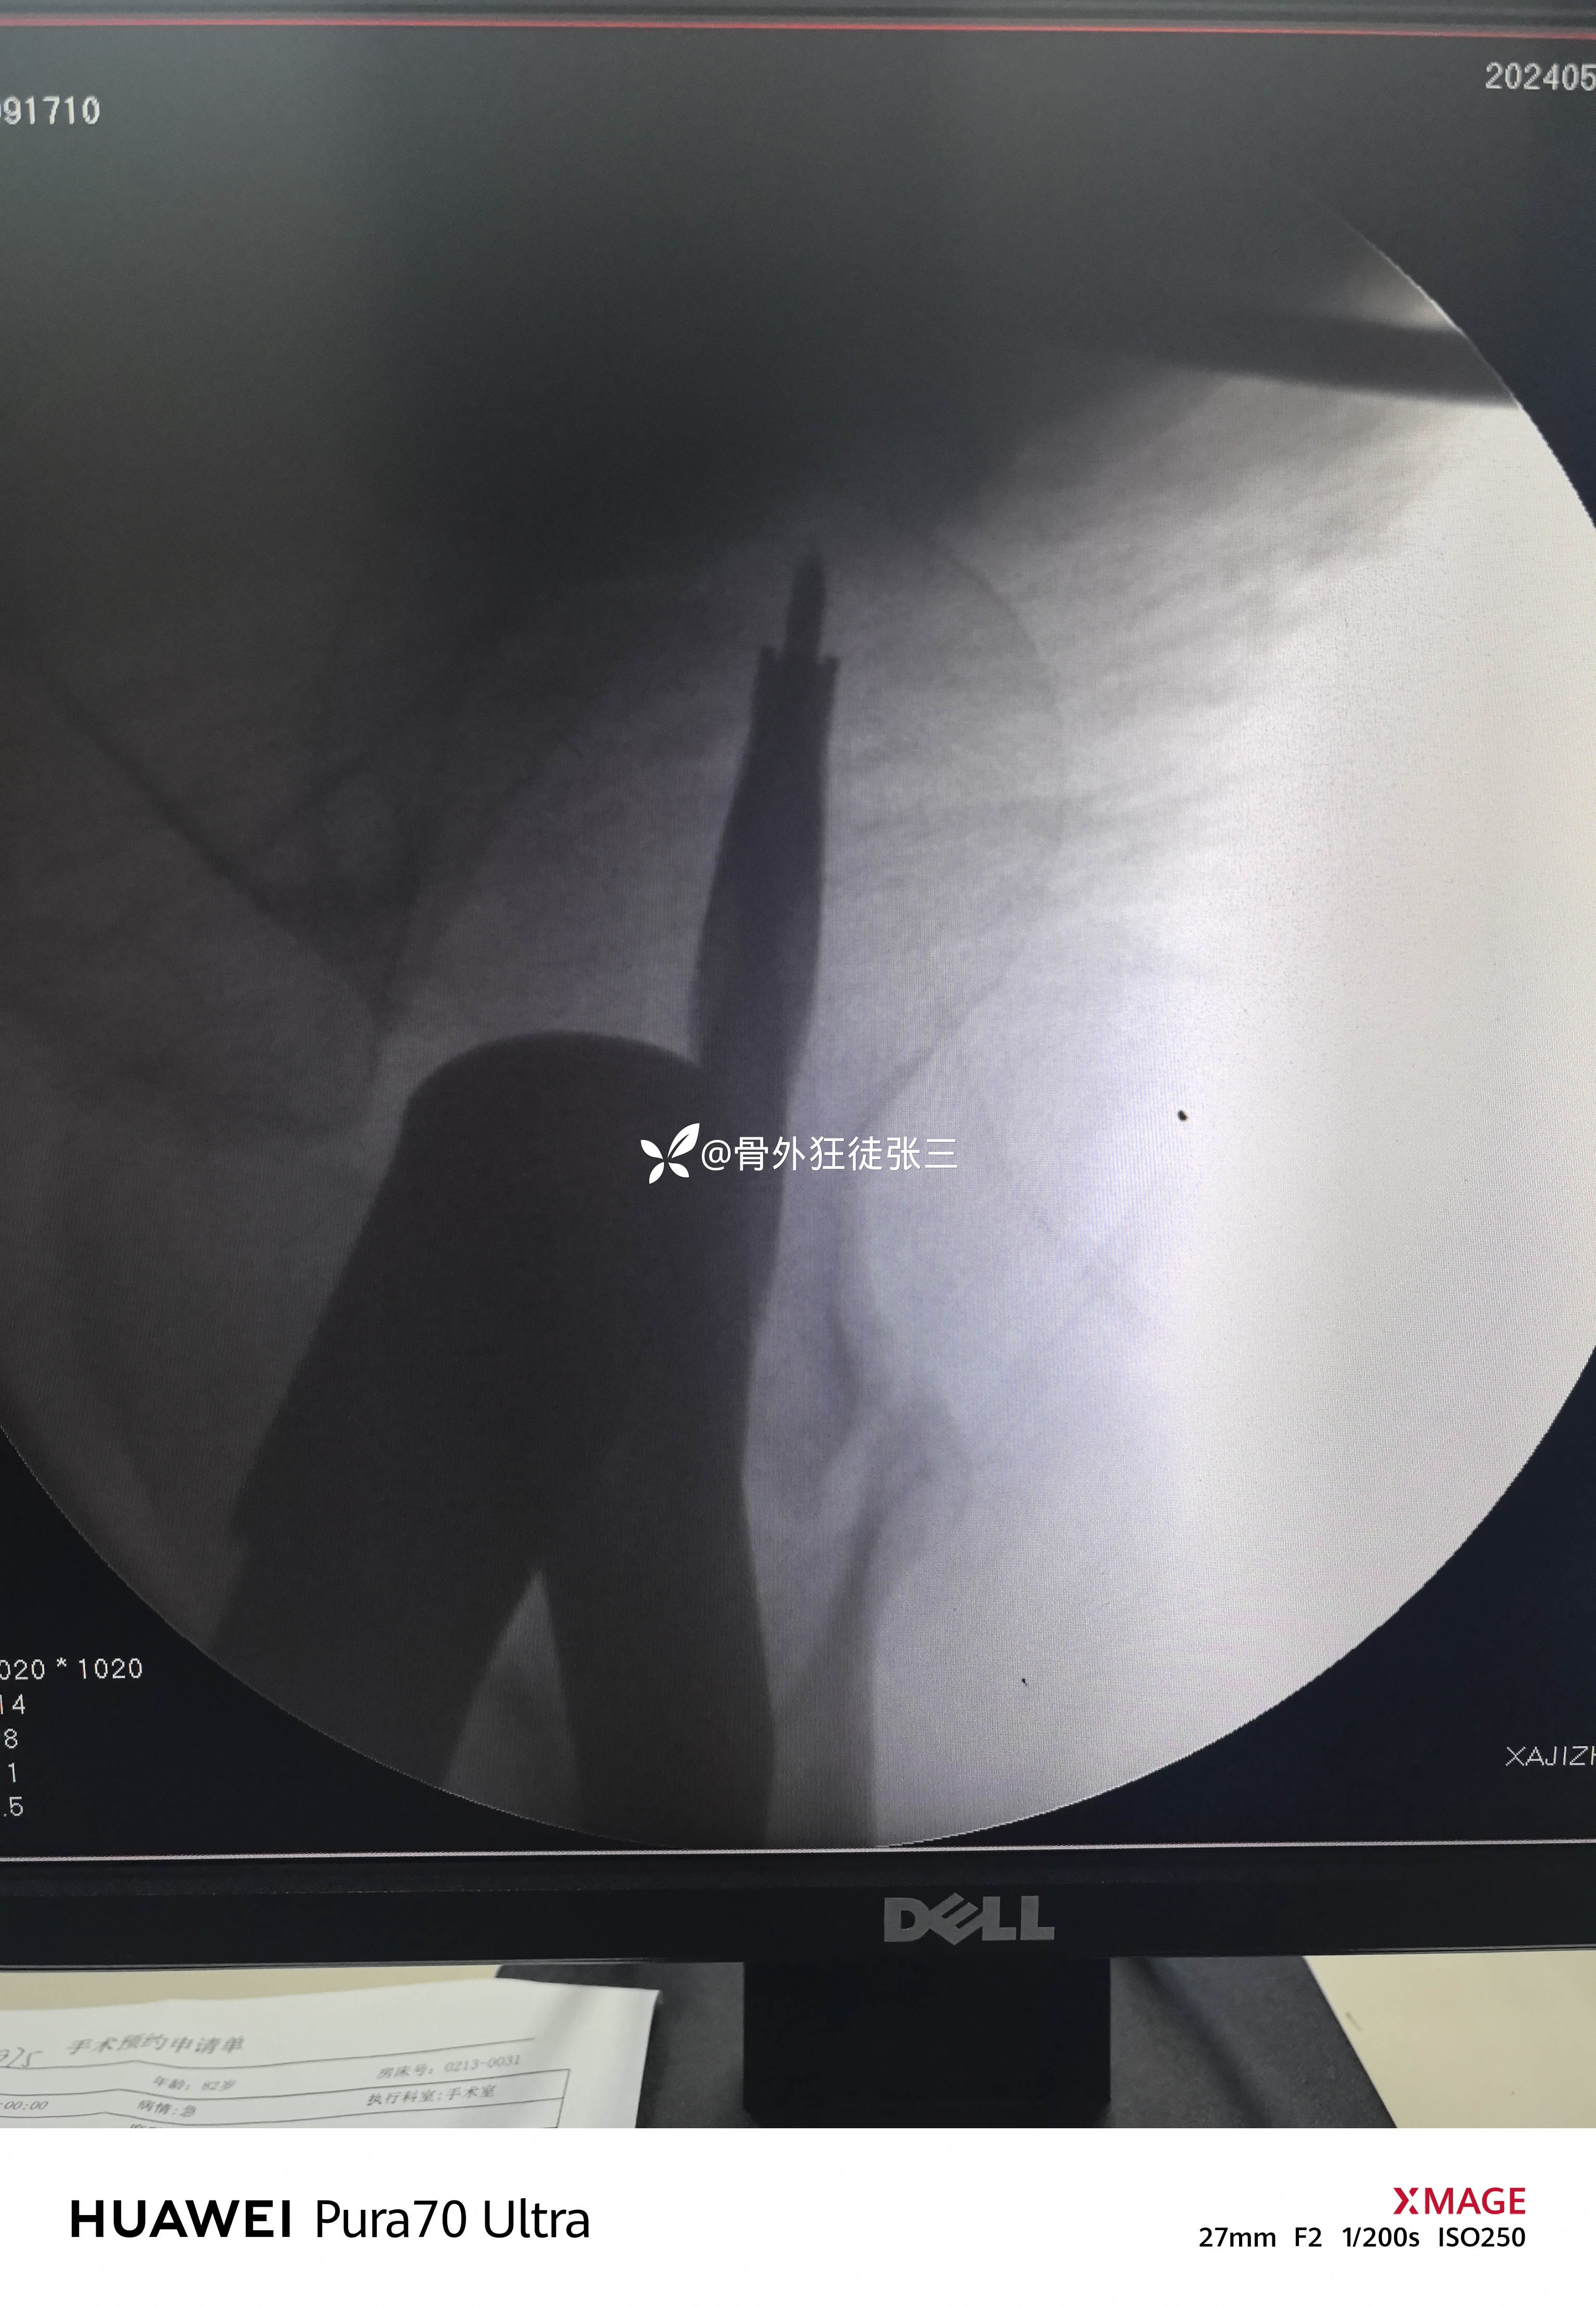

牵开器——透视正侧位——切口——确定进针点——铰刀开口——开口钻开口——金手指——导针置入——直接使用170 mmX12 mm主钉插入——调整前倾主钉深度和前倾——透视正位中下1/3,侧位基本居中——远端锁钉——近端锁尾端尾帽,——再次透视正、侧、蛙位——冲洗、缝合1-1-3 ——09:37-10:16 ——40分钟手术结束,透视16次,每次约一分钟,手术操作20分钟。